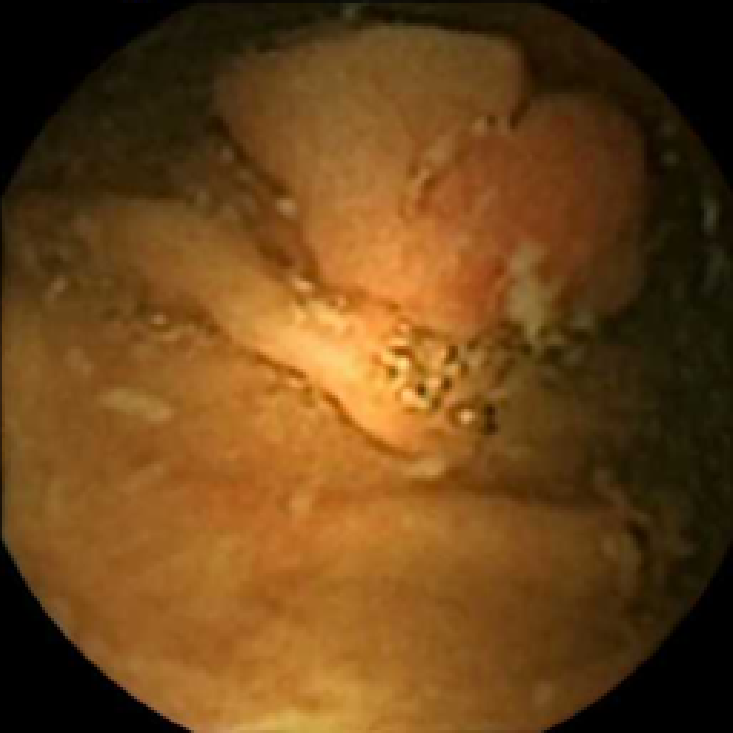

The examples of incorrect classification of frames are presented in Figure 6. The first two examples show false negatives, each highlighting a possible source of classification error. The example in column (a) shows the case where the feature corresponding to the polyp was too stretched out and thus was rejected by the eccentricity criterion (21). In contrast, the feature corresponding to the polyp in column (b) has passed the combined geometric criterion (22), but the radius was below the threshold of the binary classifier. Examples in columns (c) and (d) show the two sources of possible false positives. The false positive detection in column (c) is due to insufficient illumination correction. The bright spot is not fully corrected at the pre-processing stage and subsequently generates a polyp-like feature in the mid-pass filtered frame that happens to pass through all the criteria. Finally, in column (d) a mucosal fold is classified as polyp. Note that such cases are the most difficult to deal with, as the mucosal folds can often be hard to distinguish from polyps even for a human operator.